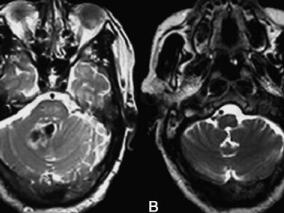

1小时条评论55岁男性,头晕、饮水呛咳、四肢乏力4个月余。头颅MRI提示右侧小脑齿状核陈旧性出血,左侧延髓体积增大。这是何病?该如何治疗? 临床资料 患者男性,55岁,主因头晕、饮水呛咳、四肢乏力4个月余于2008年2月19日入院。于2007年10月出现头晕、饮水呛咳、四肢乏力,...